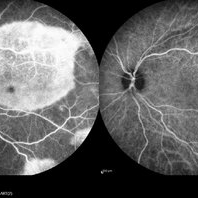

RPE rip in a case of Idiopathic polypoidal choroidopathy RPE rip in a case of Idiopathic polypoidal choroidopathyOct 23 2022 by Anjana Mirajkar, MS Ophthalmology Montage of Fluorescein angiography in a of 61 year old male with RPE rip in a case of Idiopathic Polypoidal Choroidopathy. Photographer: Dr. Anjana Mirajkar -Retina Foundation, Ahmedabad Condition/keywords: Idiopathic polypoidal choroidopathy, RPE rip